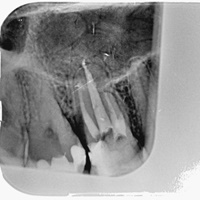

Pacjent z bólem, nieudana próba udrożnienia kanałów pod mikroskopem. Decyzja o resekcji korzenia policzkowego dalszego. RTG kontrolne rok po zabiegu.